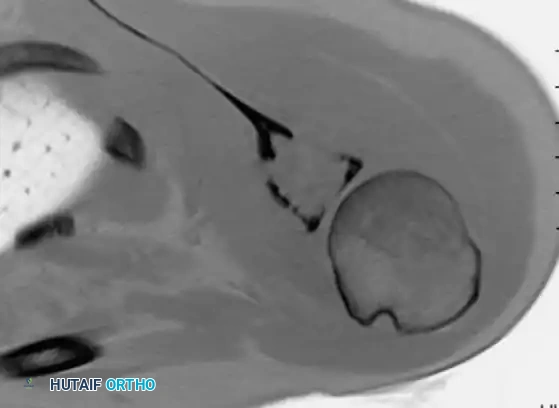

Thorough pre-operative planning is the cornerstone of successful oncologic surgery. An incisional or core needle biopsy is mandatory for definitive histological diagnosis prior to any definitive resection.

Surgical Warning: The biopsy tract must be meticulously planned. It should be placed longitudinally, directly over the tumor, and strictly within the planned definitive surgical incision. Transverse incisions or contamination of adjacent compartments will necessitate a much larger, potentially morbid resection later.

Image-guided core needle biopsy (as seen in the cross-sectional imaging above) allows for precise targeting of the most aggressive-appearing solid components of the tumor, avoiding purely cystic or necrotic areas that may yield non-diagnostic tissue.